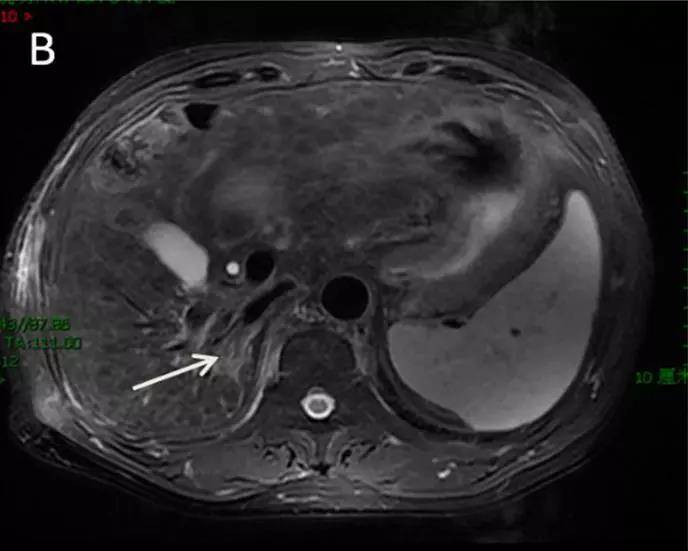

图2 治疗3个月后病灶达CR

注:图1~2 为笔者所在单位1例不可手术的HCC患者,采用SBRT技术进行治疗,单次放疗剂量10 Gy,共5次,3个月后复查肿瘤达CR。